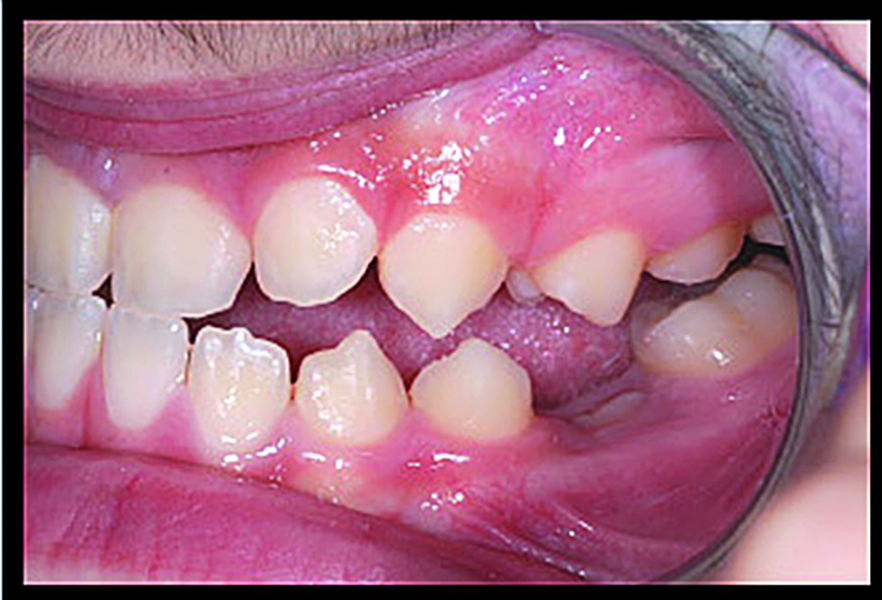

BiTurbo2 system for rapid deep overbite correction